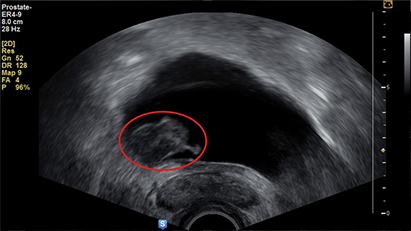

02초음파 검사는 초음파 검사기를 통해 혈뇨를 검사합니다.

초음파 검사기를 통해 혈뇨를 검사합니다.

방광암, 요로감염, 전립선염, 전립선암, 사구체신염, 신장염, 결석 등이 발생할 수 있습니다.

방광암